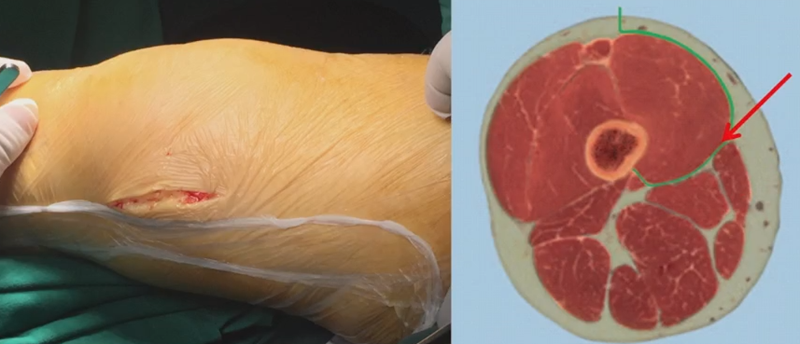

1、入路

股内侧肌间隙,在股骨远端做纵行切口,通过股内侧肌后侧间室,将股内侧肌向前方拉开,显现股骨近端远侧骨面。

2、显露-骨撬保护

操作中注意使用两把骨撬将前方及后方的软组织拉开,保护股内侧肌和后侧血管神经束。尤其是后方骨撬一定要贴近后侧骨皮质向外侧插入,可以将后侧的重要的血管神经结构保护在骨撬下方。

3、选择合页位置和截骨线

合页点的选择与HTO一样,通常需要尽可能接近畸形部位,既要有很好的骨质结构,还要有坚韧的软组织覆盖,以保证稳定性和术后有良好的血运。合页宽度不宜太长,通常保留在5mm。

合页点定位有两种方法,一种为定位在股骨外后髁上缘2mm位置,通常将此区域叫做“鹰嘴区”,以此为解剖标记法来定位合页点。

另一种通过导针从截骨入点向股骨外后髁后缘打出一条切线,此切线与外侧骨皮质的交点,也可作为合页点,这种方法称为导针法。这两种方法在手术之中是可以互为验证的。

合页点处于松质骨区,易形变区,如选择周边区域较脆易折断。另外合页点后方有小腿三头肌的附着点,有很好的的软组织和血运,综合来说作为合页非常合理。